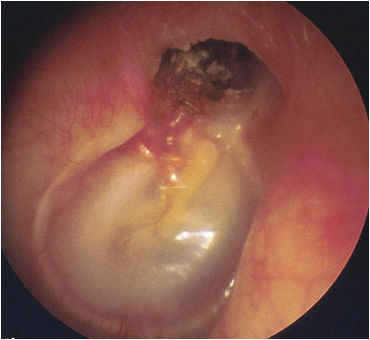

中耳炎长期不愈导致听力下降、胆脂瘤型中耳炎

渗出性中耳炎鼓室内积液,粘连性中耳炎中耳传导功能受限制,急、慢性化脓性中耳炎导致鼓膜穿孔等的耳聋多是传导性耳聋。胆脂瘤型中耳炎由于破坏明显,有时可引起混合性耳聋甚至神经性耳聋。儿童期渗出性中耳炎是多发病,一般可以通过药物或鼓膜置管治愈,但治疗不及时会形成“胶耳”(积液变粘稠不能排出的意思),轻则造成粘连性中耳炎,严重的会导致胆脂瘤型中耳炎。中耳炎引起传导性耳聋可以通过不同的方法包括药物、鼓室成形术、听骨链重建等来解决。神经性聋或者混合性聋中提高听力的效果差,严重的感音神经性聋需要配带助听器。